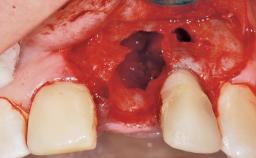

A 30-year-old female patient had lost tooth 21 and was referred to our clinic for consultation and treatment. Due to advanced apical infection, tooth 21 had been extracted two months earlier at another clinic and an acrylic-resin tooth had been bonded to the adjacent teeth. The patient desired implant treatment to avoid any damage to the adjacent natural teeth. While the patient had no history of any systemic disorder, she was a heavy smoker and exhibited medium to advanced periodontitis in the entire jaw. After the initial treatment to achieve a pocket probing depth of less than 4 mm and no bleeding on probing, a decrease in the height of the papillae mesial and distal to the extraction site and overall gingival recession were observed.

Bone Volume Deficient horizontally, requiring prior grafting